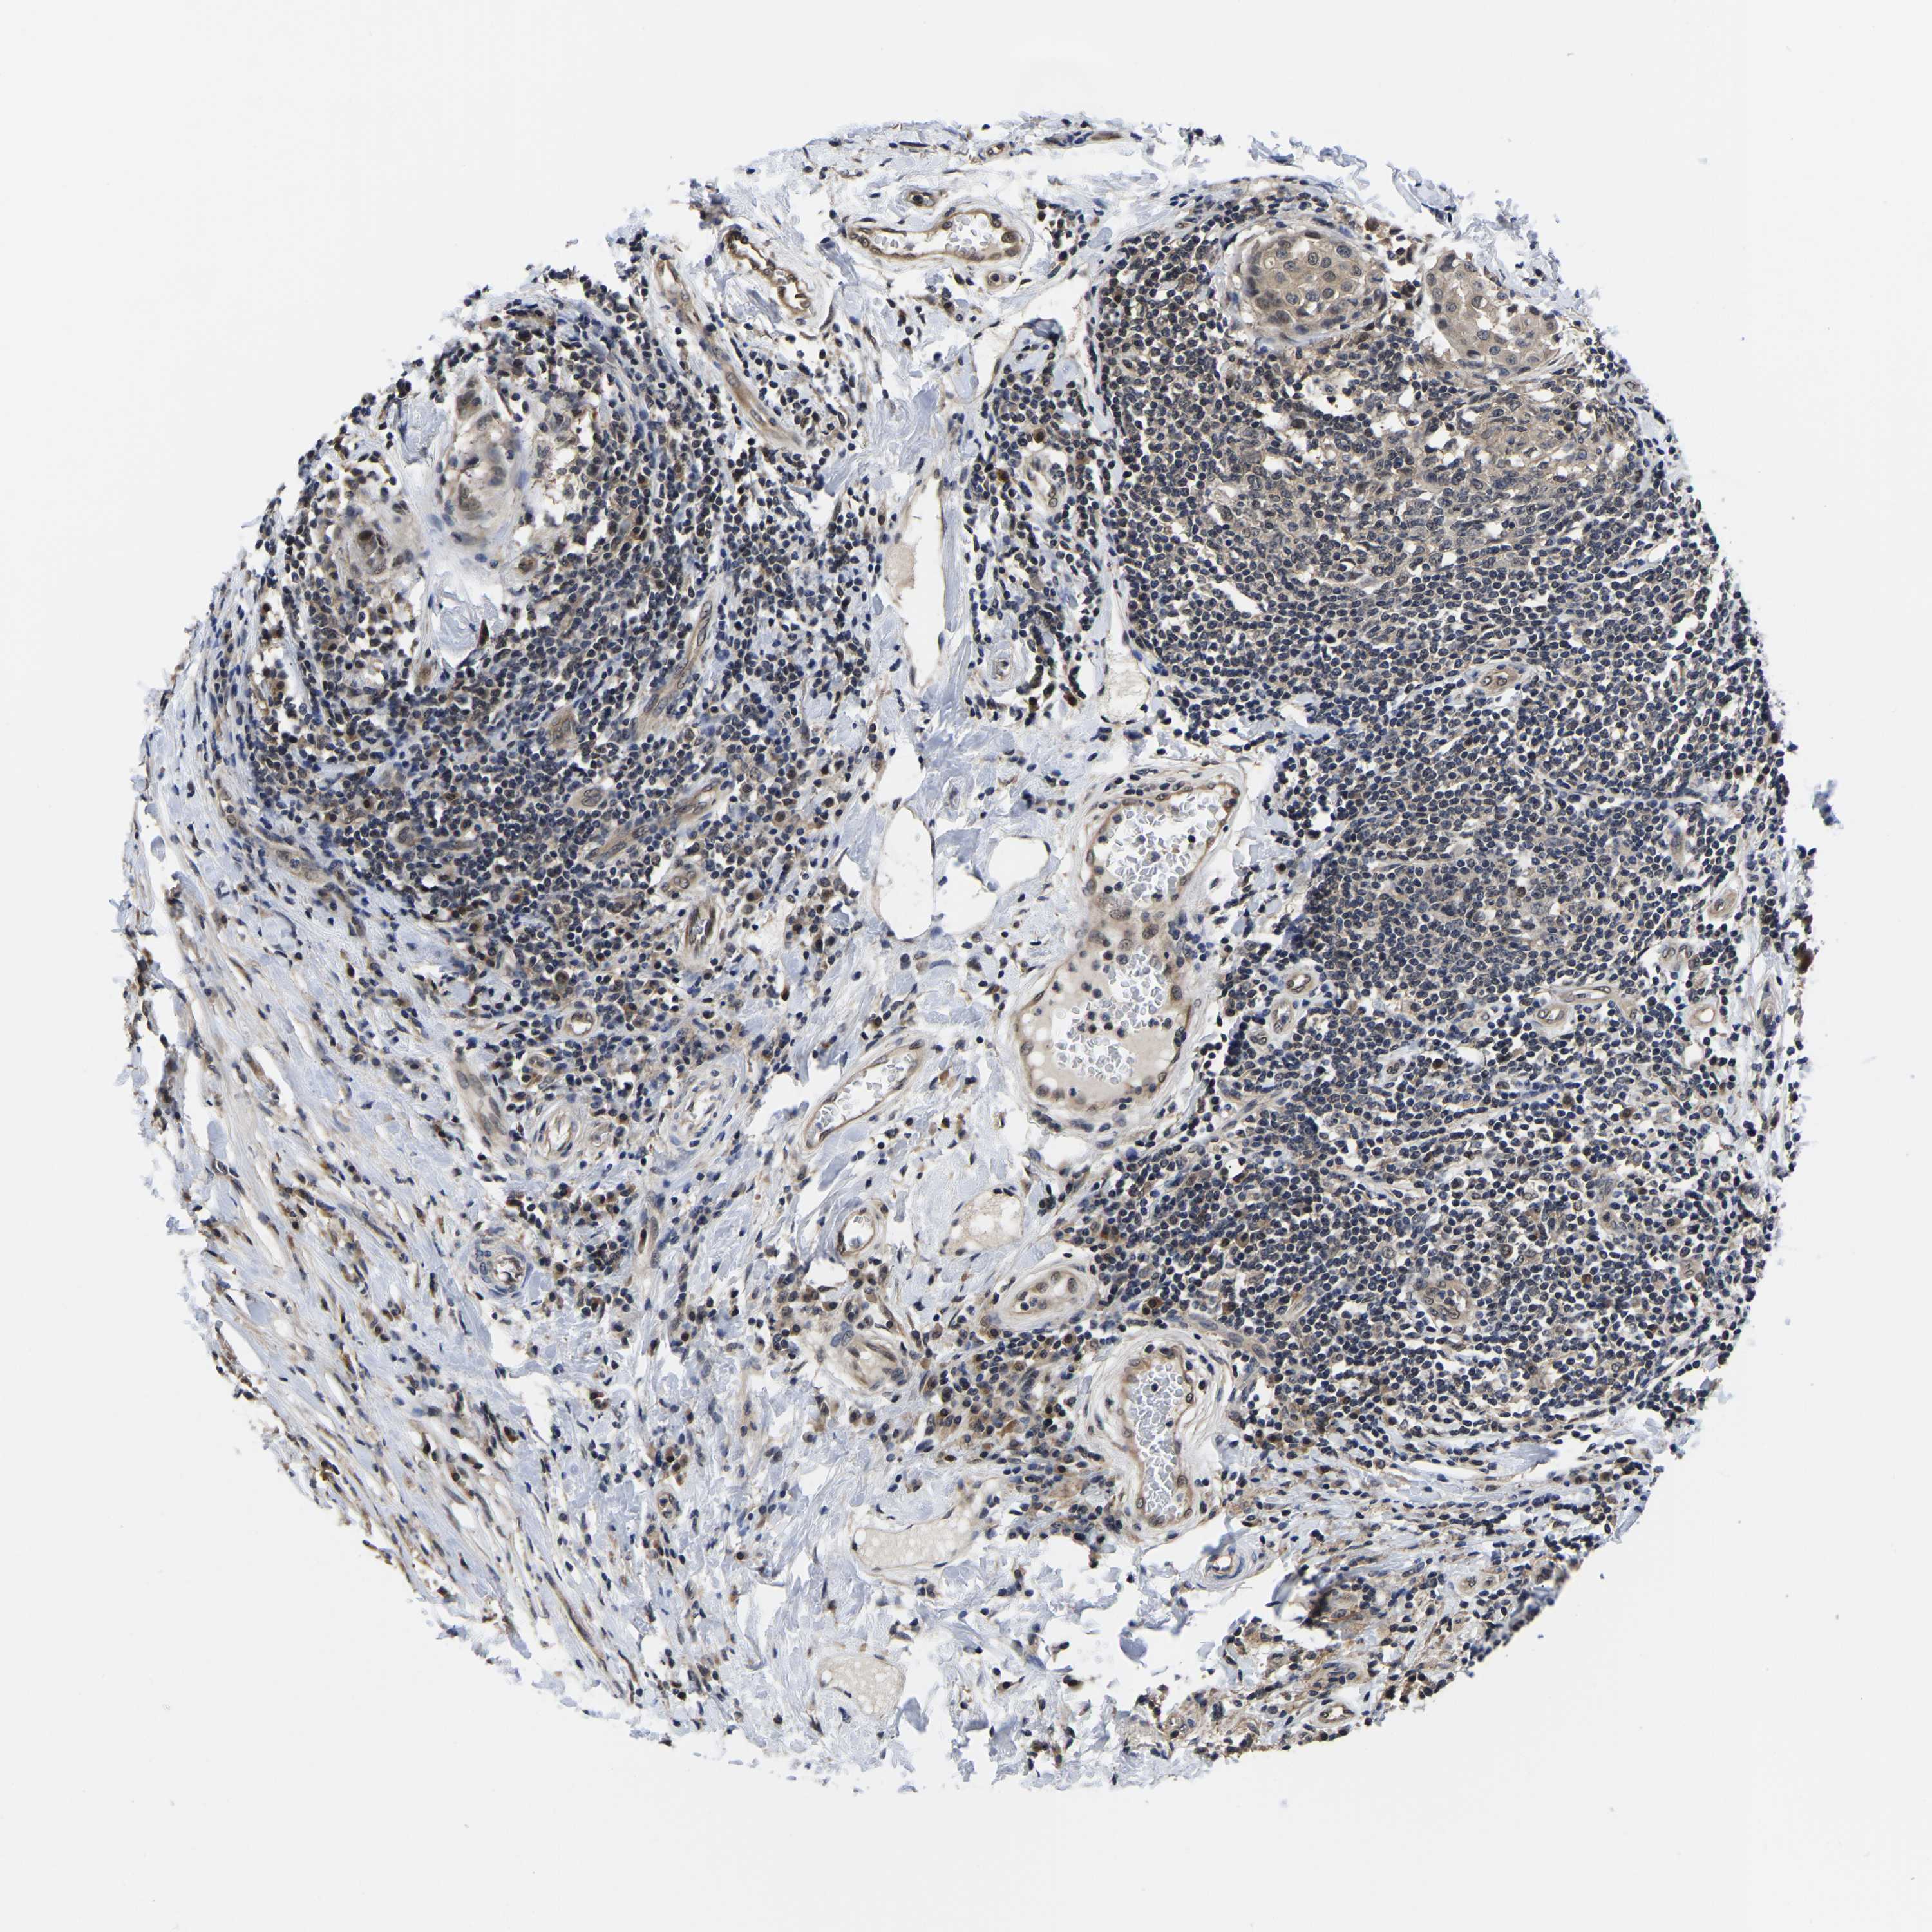

CANCER BREAST CANCER Show tissue menu

BRCA TCGA BRCA VALIDATION PROTEIN EXPRESSION

Breast cancer

Human cancer

Breast invasive carcinoma